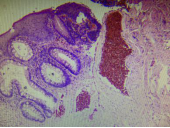

內痔位于齒狀線以上,是直腸上靜脈叢曲張的結果。外痔是直腸下靜脈叢曲張所致,位于齒狀線以下。由于直腸上、下靜脈叢間有豐富的吻合支,其中一個靜脈叢的曲張變化可波及另一靜脈叢,從而導致內、外痔合并發生,形成混合痔。鏡下,外痔表明由鱗狀上皮被覆,內痔則覆以柱狀上皮,其下主要由擴張、薄壁而充滿血液的靜脈組成,靜脈內常有血栓形成。此外,可見多少不等的漿細胞、淋巴細胞和中性粒細胞浸潤,表面可有潰瘍形成。

外痔 內痔 混合痔